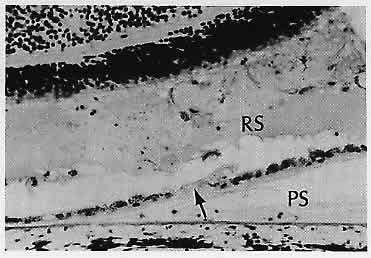

Fig. 18. Eosinophilic fluid is present in the subretinal pigment epithelial (RPE) space (PS) and in the subsensory retinal space (RS). Fluid presumably goes from the sub-RPE space into the subsensory retinal space through a break in the RPE (arrow).

Central serous choroidopathy (or central serous retinopathy, pigment epitheliopathy, or chorioretinopathy) is an idiopathic disorder usually occurring in young men. One of more leaks in the retinal pigment epithelium allow fluid from the choriocapillaris to collect in the potential space beneath the sensory retina. The result is a blister-like sensory retinal detachment with clinical metamorphopsia. On fluorescein angiography, the leakage point classically appears as a “smokestack” as the fluorescein enters the subretinal space through the leakage site. The borders of the detachment are fuzzy. In contrast, any accompanying retinal pigment epithelial detachment has sharp margins. The condition can recur, and the cause is not understood.94

A number of conditions can cause secondary retinal pigment epithelial leakage with retinal pigment epithelial and sensory retinal detachments, including scleritis, inflammation or tumors of the choroid (e.g., nevus and hemangioma),95 and subretinal neovascularization.96